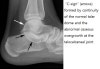

X-ray : 선천성 족근골융합증, 족근 결합(Congenital tarsal coalition, Synostosis)

Cf) 거골 부리(Talar beak)

거골 경부의 배측에 생기는 골극입니다.

Congenital tarsal coalition에 합병되는 경우가 많고, 압박하지 않으면 증상이 없습니다.